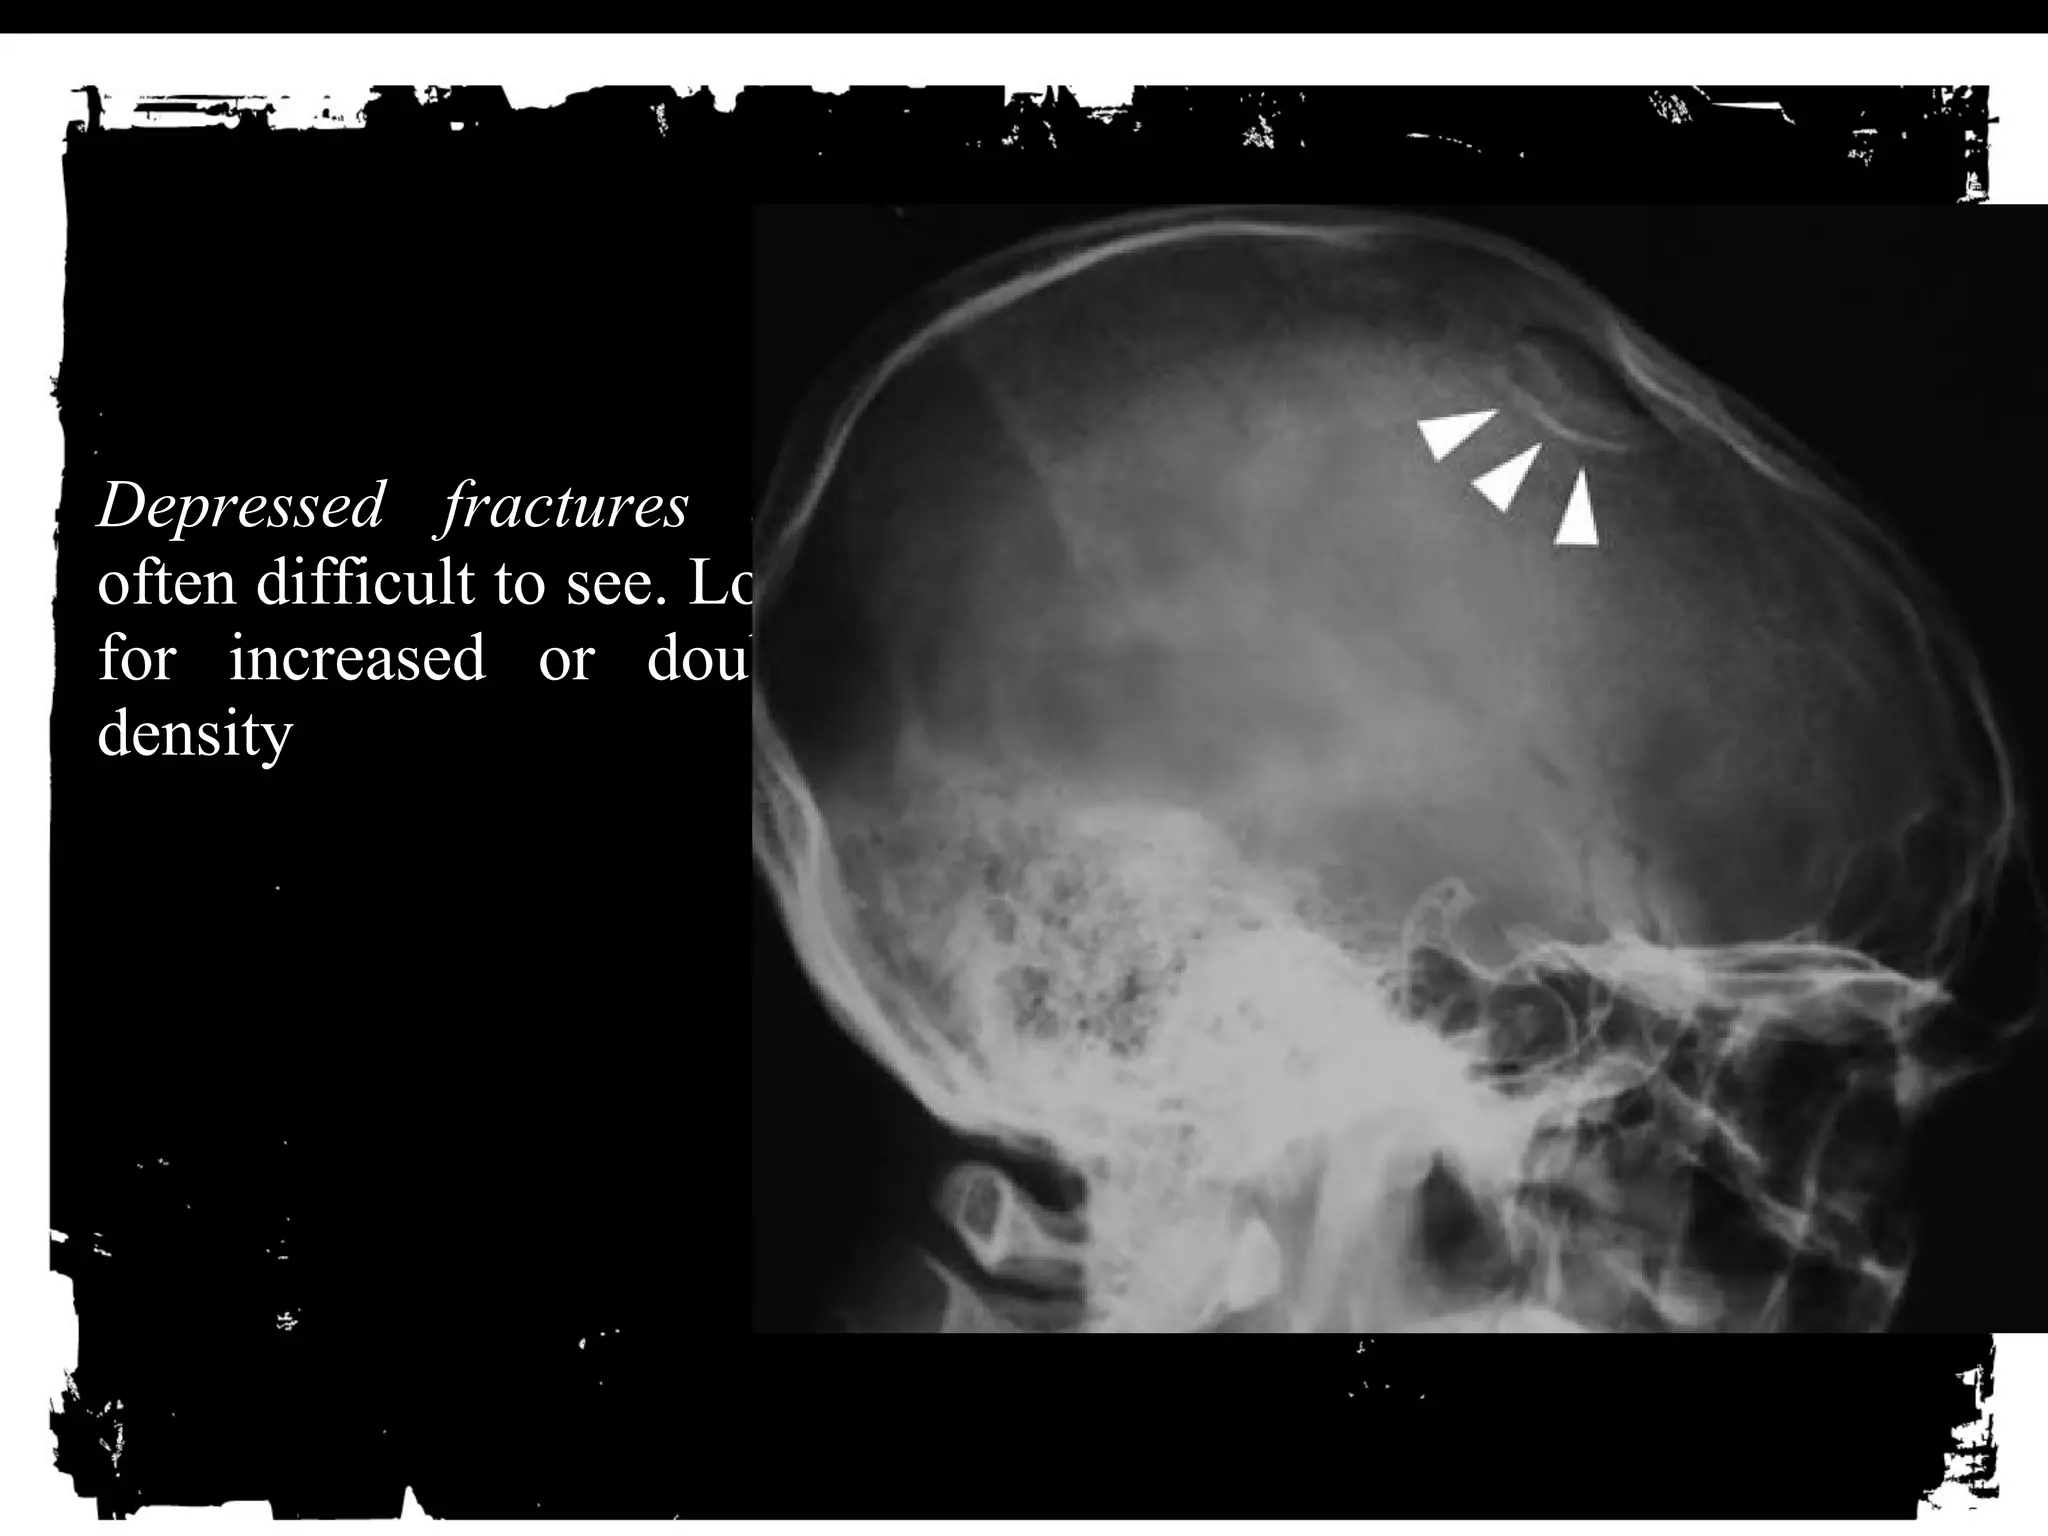

Depressed fractures are

often difficult to see. Look

for increased or double

density